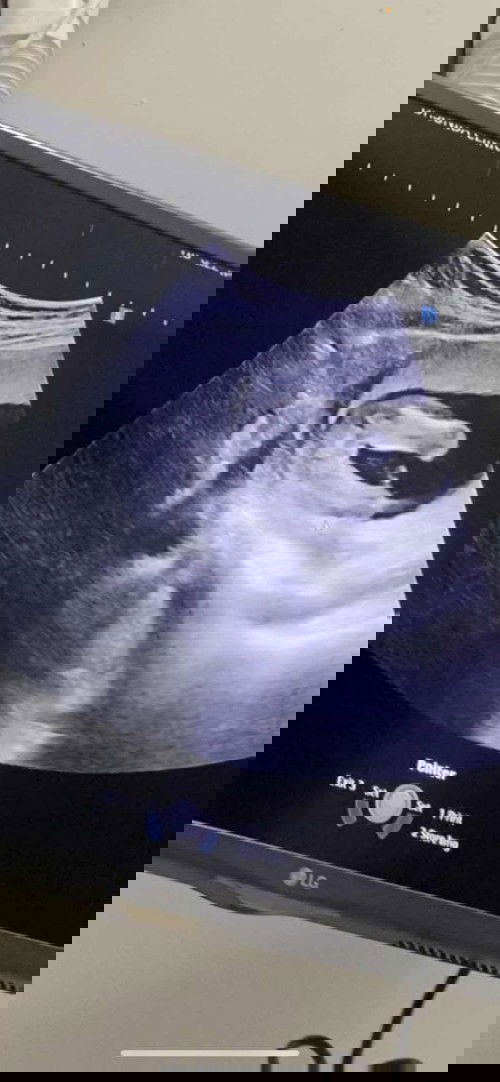

สอบถามหน่อยค่ะ พอดีวันก่อนไปหาหมอละซาวด์ดูลูก คุณหมอบอกว่าน่าจะได้เพศหญิง 80% แถมยังว่าเป็นแบนๆ แบบนี้เรียกเพศหญิงไหมคะ #อายุครรค์ตอนนี้17week 4วันค่ะ #คุณพ่อเขาอยากได้ลูกสาวมากค่ะ555 แต่ลูกสาวหรือชายก็รักหมดค่ะ 🤣🥰👼🏻